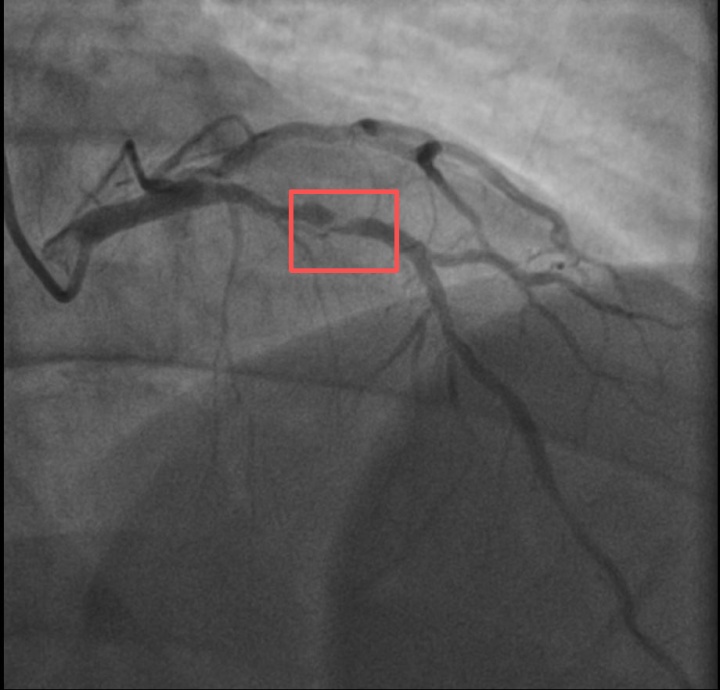

介入治疗前影像图

浙江医院心血管内科的医生分析,剧烈运动导致这位患者心脏的不稳定斑块破裂,进而造成前降支近段次全闭塞。所幸送医及时,孙先生的身体险情被化解。

介入治疗后影像图